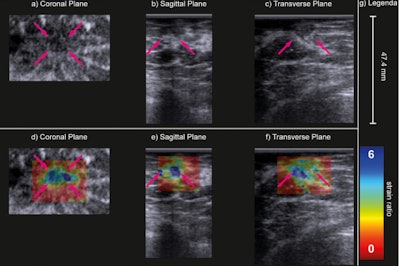

B-mode (a–c) and strain ratio (d–f) images of a carcinoma of unknown type in the coronal (a, d), sagittal (b, e) and transverse (c, f) planes. In the strain images (d–f), the maximal principal strain ratios are superimposed on the B-mode images of the top row. The purple arrows indicate the lesion. Image courtesy of Ultrasound in Medicine & Biology. Image available for fair use under creative commons license.